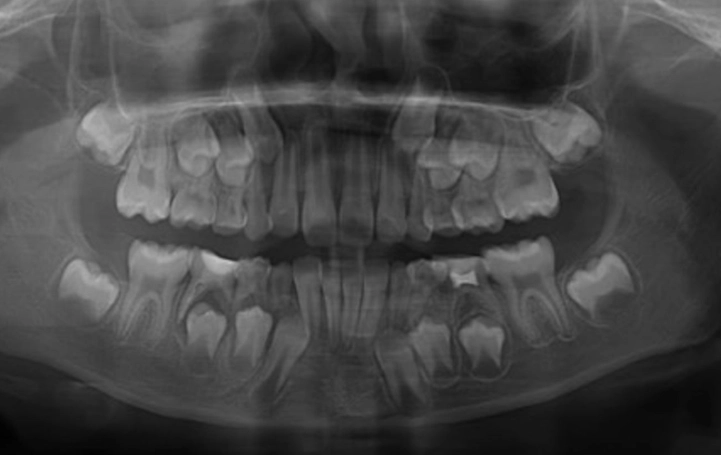

- The Gutta-Percha Test: This is a classic move. The dentist might take a very thin, flexible point (called a gutta-percha point) and gently insert it into the opening of the sinus tract. Then they take an X-ray. The point will often show up on the X-ray tracing a path directly to the culprit root tip. It's like following a road map to the problem.

- The X-ray (Radiograph): This is crucial. A standard dental X-ray might show a dark area around the root tip of the tooth. This is the bone loss caused by the infection. It looks like a shadow or a halo. Sometimes, the sinus tract itself is visible as a faint dark line. For complex cases, a 3D cone-beam CT scan might be used to see the exact size and location of the abscess and bone damage.

Putting all this together—the bump, the tooth history, the clinical tests, and the X-ray evidence—confirms a diagnosis of a chronic periapical abscess with a draining sinus.